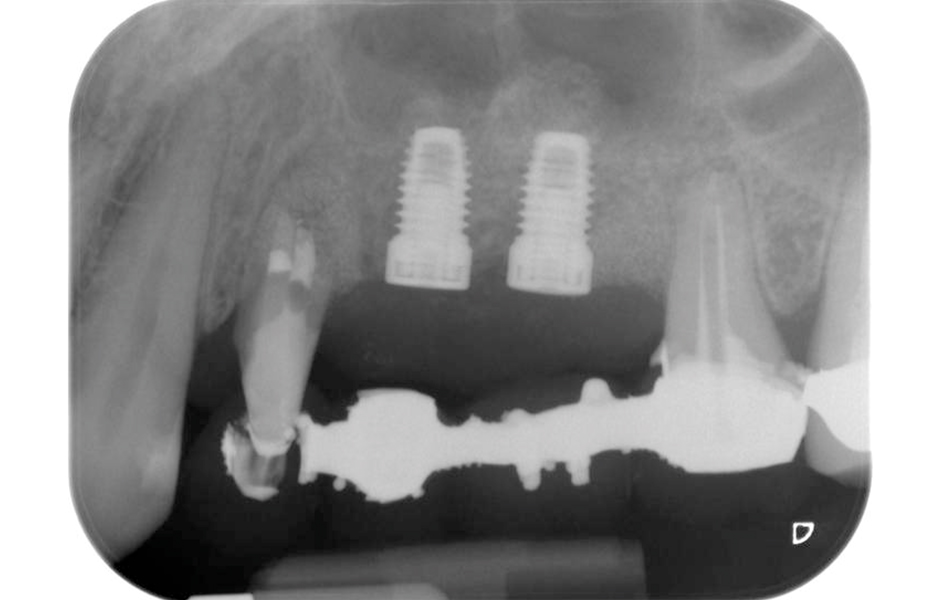

Nakonec, po provedení periosteálního řezu, bylo místo spolu s koronálně posunutým lalokem pasivně sešito vstřebatelným šicím materiálem 5-0 (obr. 15). Pooperační RTG snímek prokázal, že jsou oba implantáty ve správné vertikální pozici (obr. 16).

Pooperační RTG snímek zachycující zavedené implantáty s kostní náhradou transplantovanou kolem apexů při vnitřním sinus liftu – kolem kořenů zubu 24 je vidět i materiál z GTR procedury.